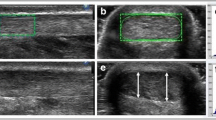

The thickness of the AT is assessed on axial T2-weighted images, coregistered side by side with sagittal fs PD‑w TSE images, to ensure that the level of greatest thickness is measured. The maximum distance from the anterior to the posterior margin of the tendon in relation to the spiral orientation of the AT on the axial T2‑w images (no strict anterior-posterior orientation) is measured in millimeters. (Fig. 1). Subsequently, the thickness of the AT is divided into 4 groups from ≤7 mm (30 points) to ≥13 mm (0 points).

Case example of a 51-year-old female patient with pain in the AT for 2 months. The maximum thickness of the AT from anterior to posterior, perpendicular to the coronal axis of the AT, on the axial T2‑w image (a; double-headed arrow), was 9.7 mm (20 points). Furthermore, the patient presented with a partial tear (10 points) and fluid-like signal intensity (0 points; long arrow) on the sagittal PD‑w TSE image (b). Associated pathologies (20 points): no Haglund exostosis (minus 0 points; parallel lines (c)), no calcaneal bone marrow edema or cysts (b) but an ossification at the tendon insertion area (–5 points; star) on the T1‑m sagittal image (c); no edema of Kager’s fat pad but slight signal increase along the AT indicating a peritendinitis (b) (–5 points; small arrows); positive retrocalcaneal bursitis (b) (–5 points; curved arrow). Total VIMAT score = 35 points